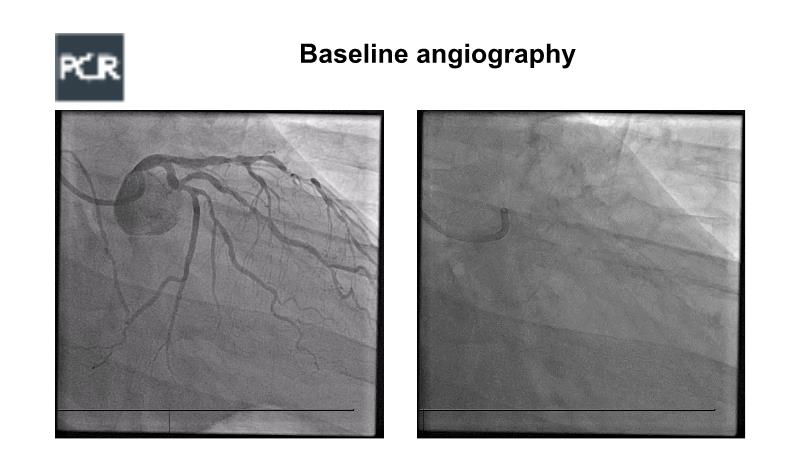

A hybrid approach in complex PCI: can DES and DCB be complementary?

Watch this case-based session to follow discussion about how to choose between DES & DCB, how both can be complementary in diffuse disease as well as in complex PCI, and how physiology and imaging can help guiding PCI, and follow a patient's treatment live.